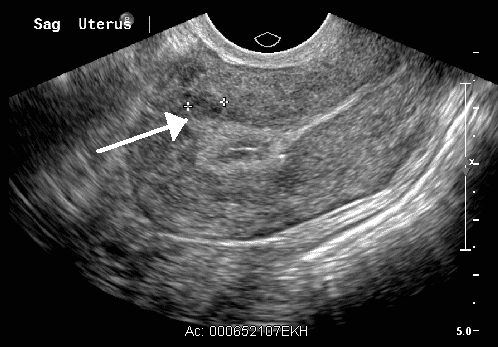

Fig 2

An intramural fibroid on pelvic ultrasound.